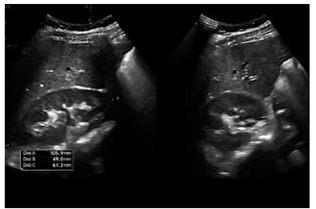

Ultrassonografia renal: rins de tamanho normal, sem alterações estruturais significativas.

(Arquivo pessoal; imagem usada com autorização)